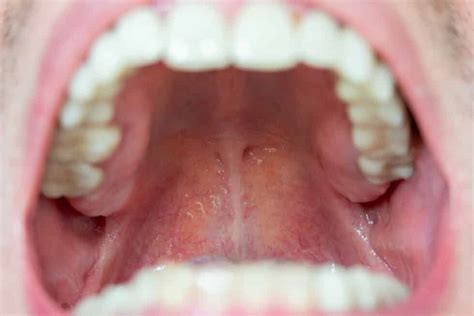

Para identificar posibles síntomas, es crucial conocer el aspecto de un paladar sano. Este debe ser rosado y uniforme. Las señales de alerta incluyen:

- Cambio de tonalidad (amarillento, rojo vivo, blanquecino).

- Aparición de llagas.

- Sensación de boca seca.

- Escozor.

- Malestar general en la boca.